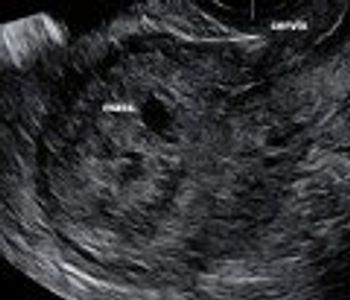

Postabortal placental polyps and uterine arteriovenous malformations can look identical on ultrasonography. Read how saline instillation sonohysterography helped discern the diagnosis.

Challenge your diagnostic skills: Can you identify this finding in the fetal abdomen?